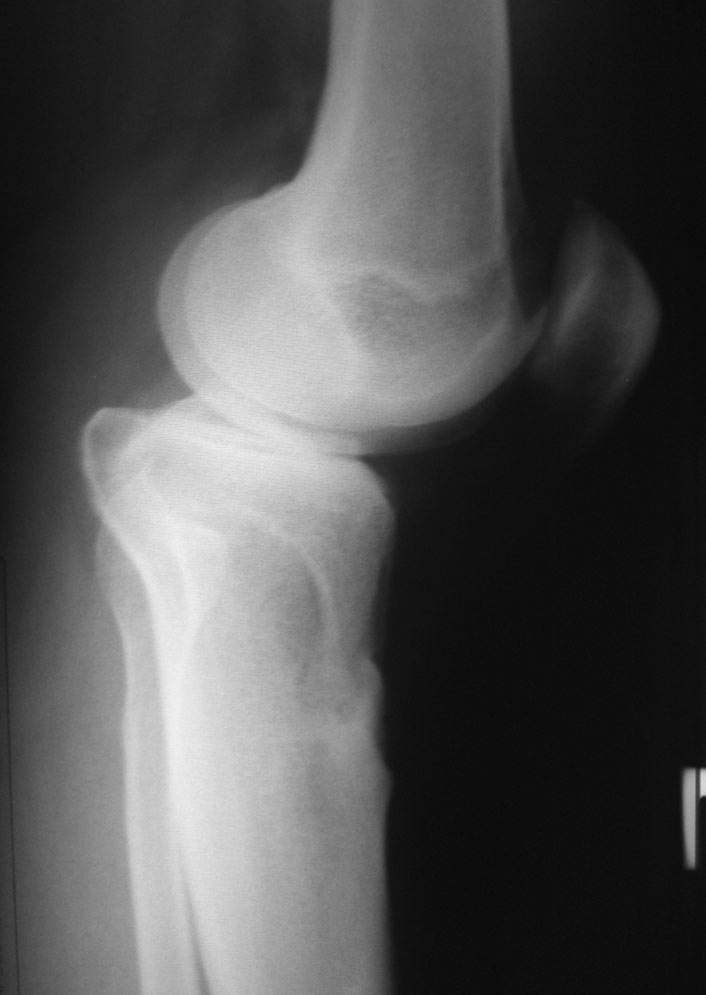

пациент наконец то объявился вновь и мы смогли выполнить новые снимки как лежа так и в нагрузке

Имя     : obe-stoya.jpg

Тип     : image/jpeg

Размер  : 23353 байтов

Описание: отсутствует

Url     : http://weborto.net:8080/pipermail/ortho/attachments/20080714/b21730ce/attachment-0005.jpg